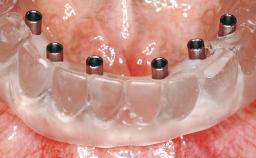

Conventional Loading of Eight Implants in the Maxilla and Final Restoration with a Full-Arch Gold-Ceramic FDP

A 35-year-old Caucasian female presenting with advanced periodontal disease involving both the maxillary and the mandibular dentition was referred for evaluation. The patient, a non-smoker in good general health, requested treatment for recurrent periodontal abscesses, tooth mobility, and discomfort during chewing, as well as restoration of her missing teeth with a fixed prosthesis to improve mastication and esthetics. All residual maxillary teeth exhibited plaque deposits, deep pockets, bleeding on probing, and class III mobility and were evaluated as hopeless. All residual mandibular teeth except tooth 37 could be maintained after periodontal therapy.

# of Implants 8

Type of Implants One-Piece

Prosthesis Type FDP